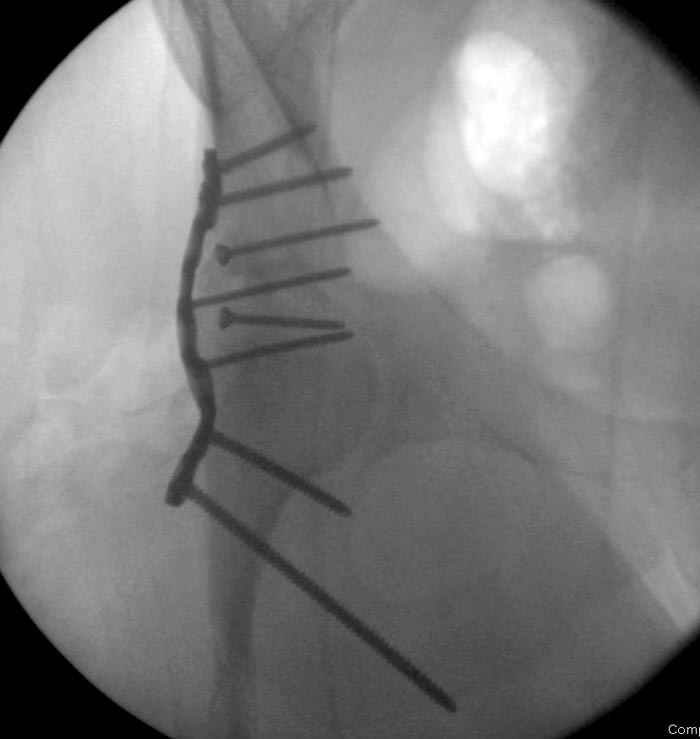

7:30 начало операции, больной на спине, попытка репозиции после анестезии N3, укладка больного на боку, доступ Kocher- Langenbeck, состояние седалищнего нерва около 2.5см кровоподтек, через joistick головка бедра приподнята, освобовождение сустава, фрагмент заднего края более 3х4 см репонирован на свое место. После промывания

сустава, репозиция вывиха (N4), фиксация фрагмента 2.7(4) мм шурупами и допольнительно реконструктивной пластиной на 8 дырок, фиксация 3.5мм шурупами проксимально и дистально.

Интраоперционные N5 косая запирательная и N6 подвздошный снимок